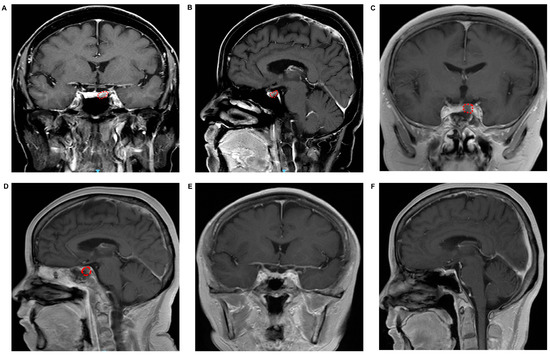

2. Materials and Methods

3. Results